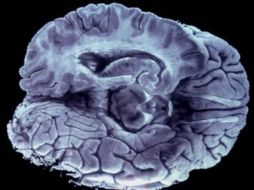

Tecnología EU lanza ambiciosa iniciativa para la exploración del cerebro humano 2 de abril de 2013 - 17:02 hs Estados Unidos Ciencia médica